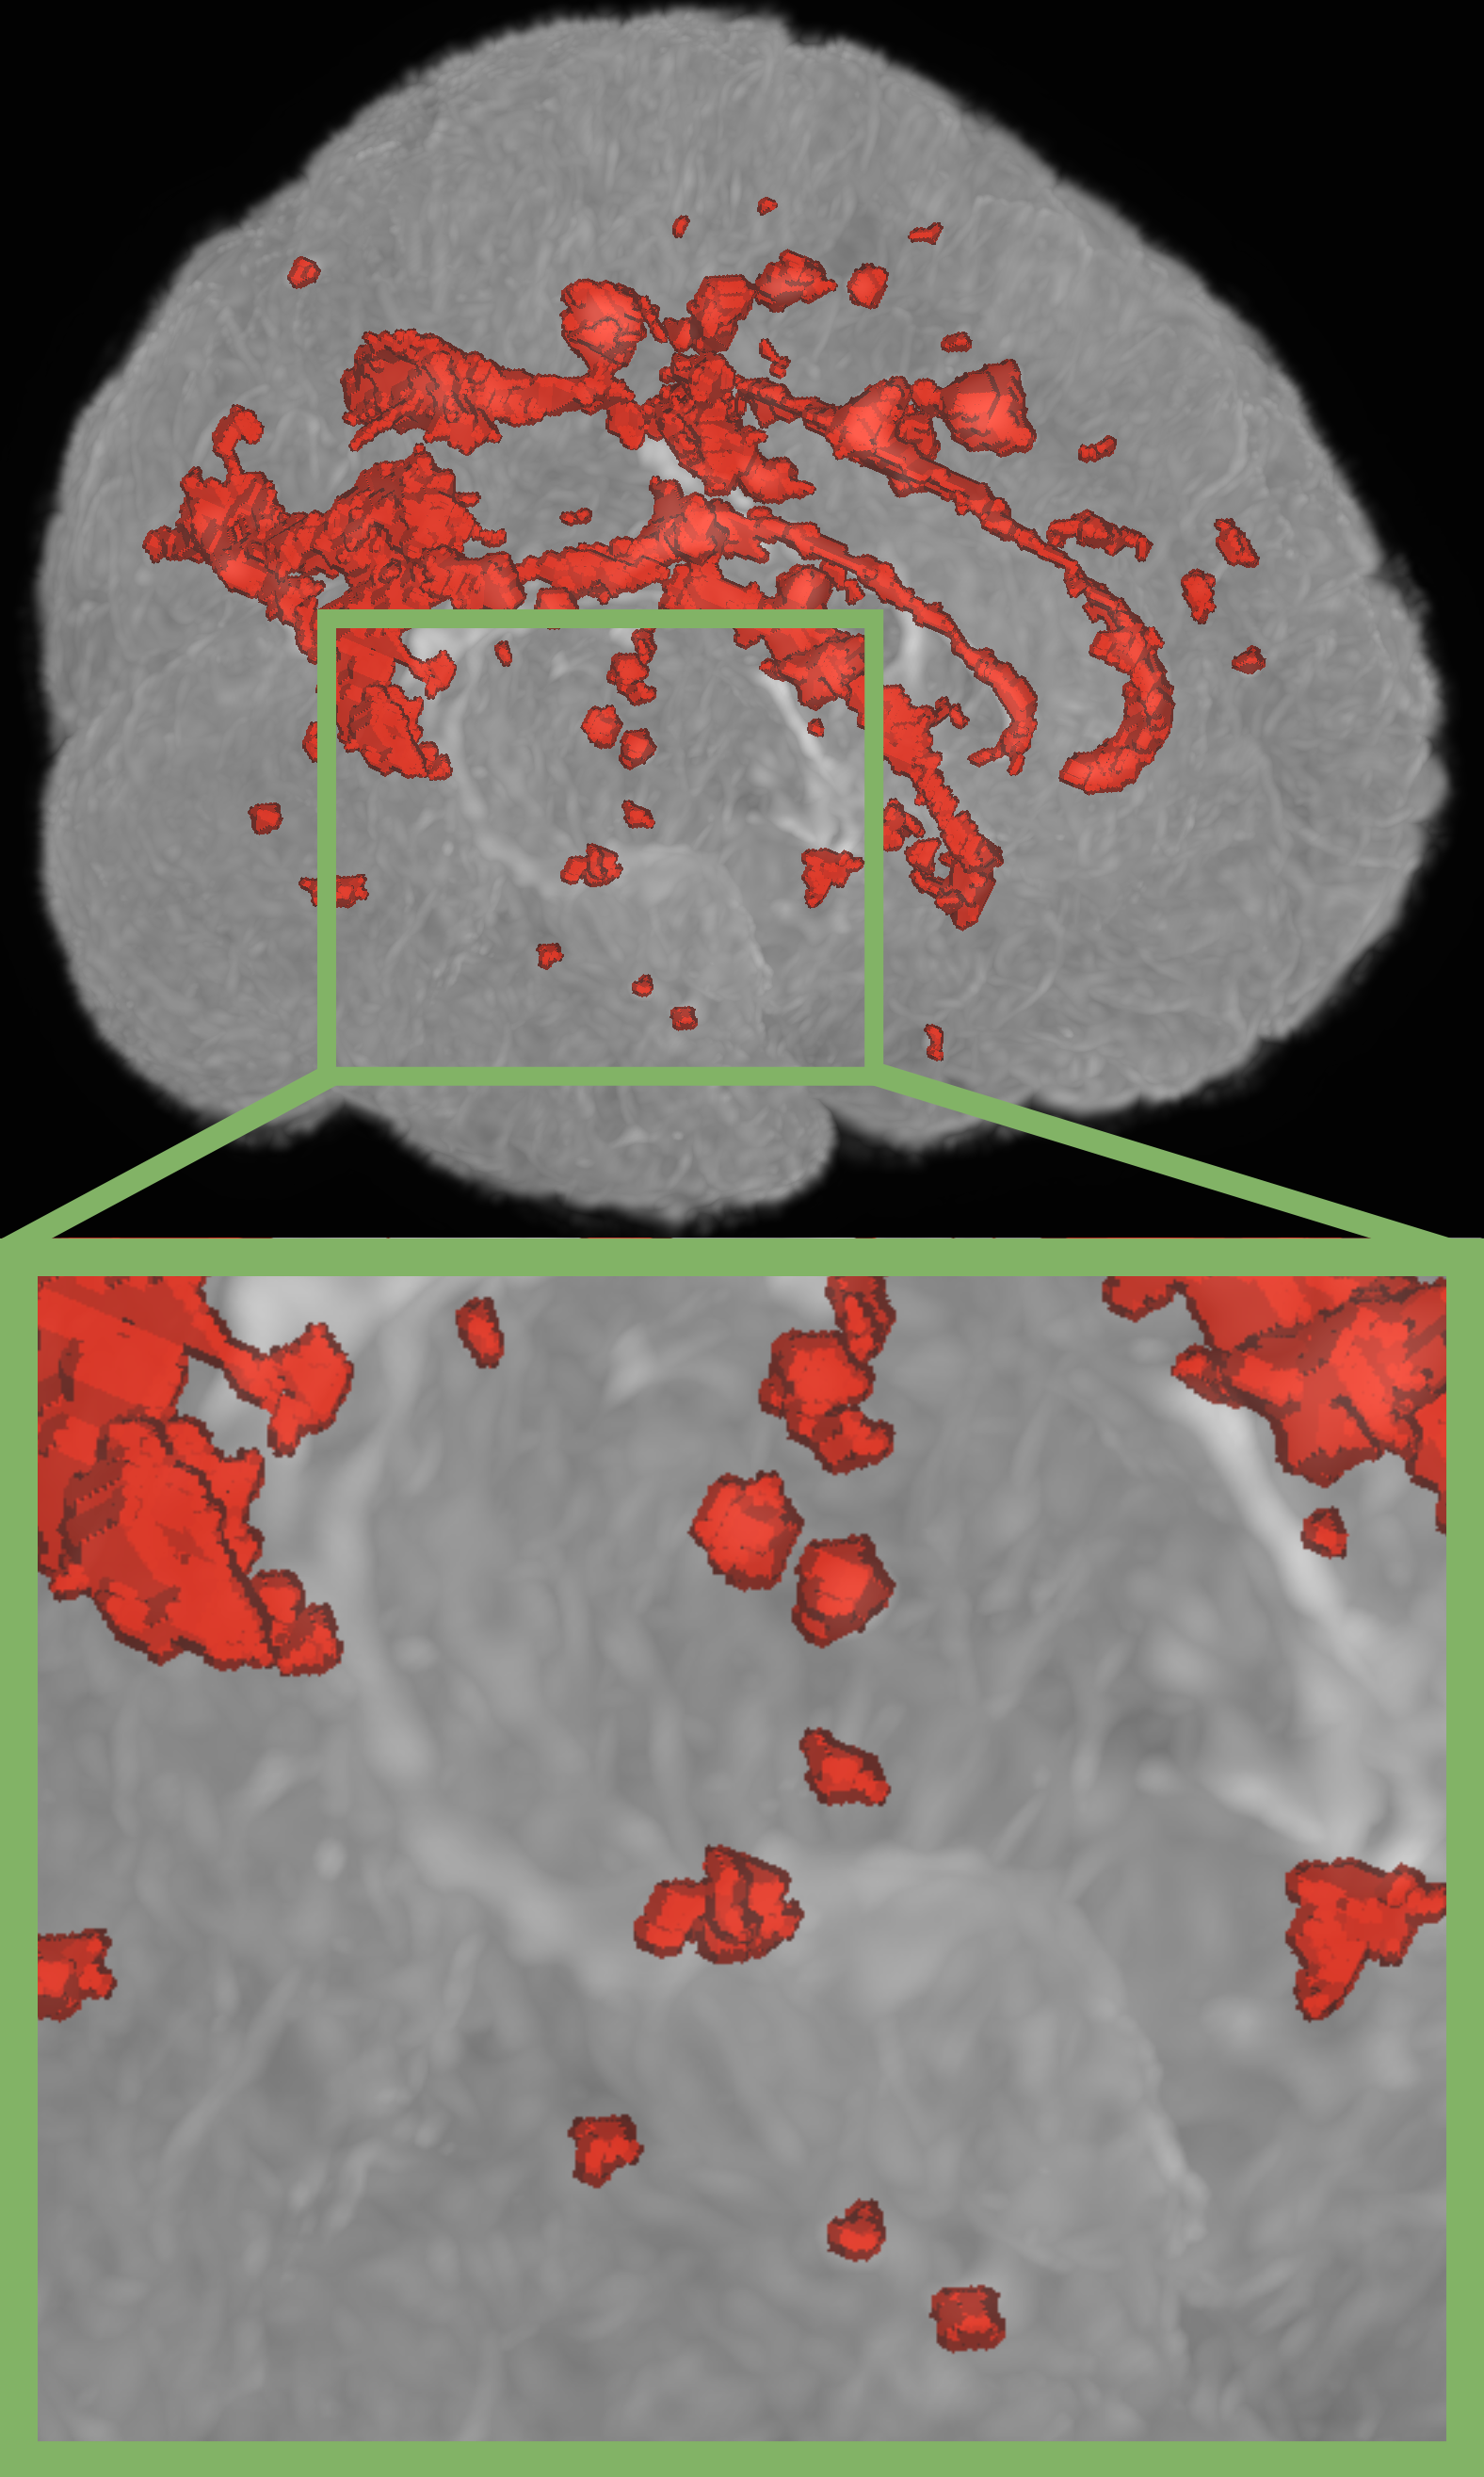

Refer to caption

(a) nnUNet[16]

(b) Szeskin et.al.[24]

(c) Difference Weighting (Ours)

(d) Ground Truth

Figure 2: Qualitative results on the Ljubljana dataset. Compared to related work, our proposed method demonstrates superior performance in volumetric delineation of MS lesions and successfully identifies lesions missed by other methods.

Table 2 illustrates SOTA performance against several established single and multi timepoint baselines on the Ljubljana dataset. We also show the generalizability of our best models on the ISBI 2015 dataset in Tab. 3 respectively. Figure 2 shows additional qualitative results on the Ljubljana dataset. Overall, we demonstrate the following findings:

Employing inductive bias via feature differences achieves SOTA performance: The integration of our novel Difference Weighting method further elevates the model’s performance, demonstrating a new state-of-the-art performance. Our proposed method improves upon nnUNet, as the best performing state-of-the-art model, by 1.45% in Dice score and 0.34mm in 95% Hausdorff distance. Notably, we see an increase of 2.01% in lesion-based F1 score, as the most important clinical metric, indicating that our approach better detects individual lesions. We also surpass the Longitudinal nnUNet indicating that the imposed inductive bias is superior over plain channel-wise concatenation.